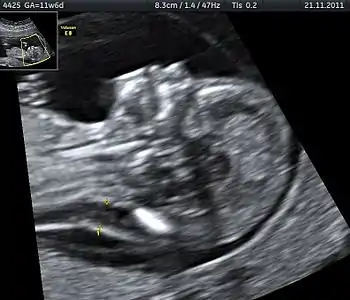

Nuchal edema in Down Syndrome Dr. W. Moroder

Trisomy 21 is a form of Down syndrome that occurs when there is an extra copy of chromosome 21. The result is a genetic condition in which a person has 47 chromosomes instead of the usual 46. During egg or sperm development the 21st chromosome does not separate during either the egg or sperm development. The result is a cell that has 24 chromosomes. This extra chromosome may cause problems with the manner in which the body and brain develop.[29]